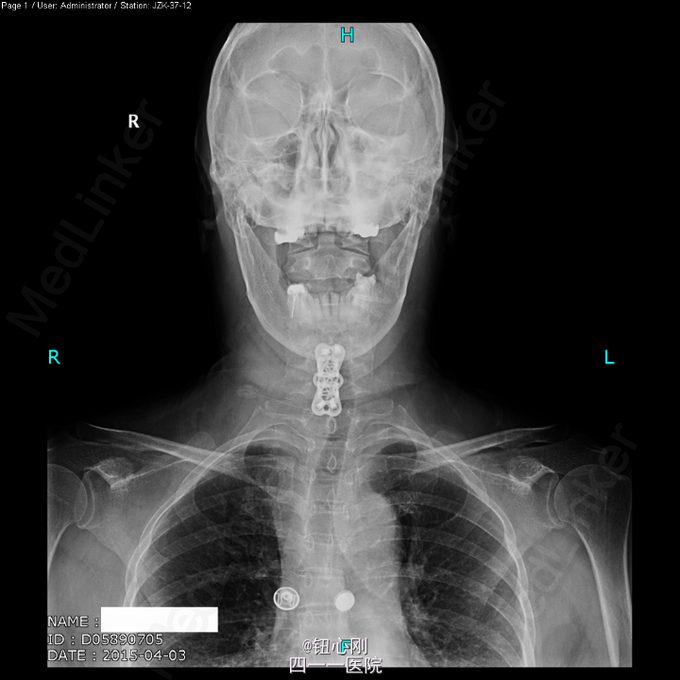

体检未见明显阳性体征。 辅助检查:血沉68mm/h,神经元特异性烯醇化酶23ug/l,余肿瘤指标正常。三大常规、肝肾功、电解质正常。 颈椎MRI、腰椎MRI及PET-CT扫描见图。

术前诊断:多椎体病变待查(转移瘤?) 诊断依据:老年女性,出现颈腰部疼痛,MRI及PET-CT扫描提示椎体多节段病变,以转移瘤可能性为大,同时血沉升高。 处理:2015-03-31在全麻下行颈6椎体病变前路次全切+钢板钛网植骨融合内固定术。术中所见:颈6椎体骨质疏松,部分硬化,未见鱼肉样组织。术后切除骨质送病理检查。 病理报告:骨小梁稀疏,其间有纤维组织,同时可见硬化死骨。 术后诊断:颈6椎体骨质疏松性骨坏死。